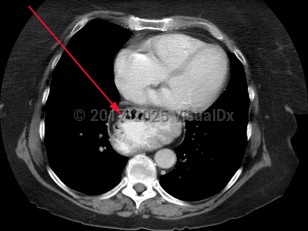

Hiatal hernias are typically asymptomatic. On occasion, patients will complain of vague abdominal discomfort. However, in most instances, they are diagnosed incidentally on cross-sectional imaging or upper endoscopy.

Hiatal hernias are classified as sliding or paraesophageal:

- Type I: sliding hernia – Most common type, due to progressive weakening of the gastroesophageal junction allowing a portion of the gastric cardia to slide upward with increased abdominal pressure, swallowing, and respiration. Patients with type I hernias are more likely to have gastroesophageal reflux disease (GERD).

- Types II, III, IV: paraesophageal hernia – Herniation includes viscera other than the gastric cardia, including gastric fundus and the colon. In type II and III hernias, the stomach becomes "inverted," possibly leading to gastric volvulus.